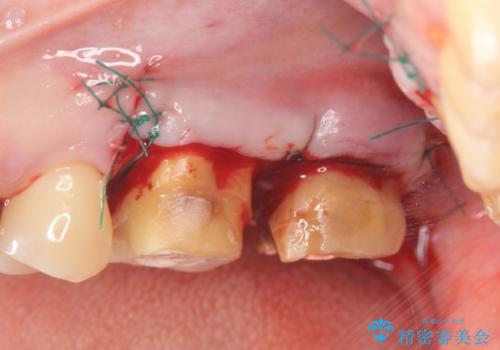

銀歯を除去したところ、虫歯が大きく再発しこのままではかぶせ直しができないような状況でした。

・深い虫歯 →歯周外科を行うことで歯ぐきの腫れを改善

・根尖性歯周炎 →精密根管治療